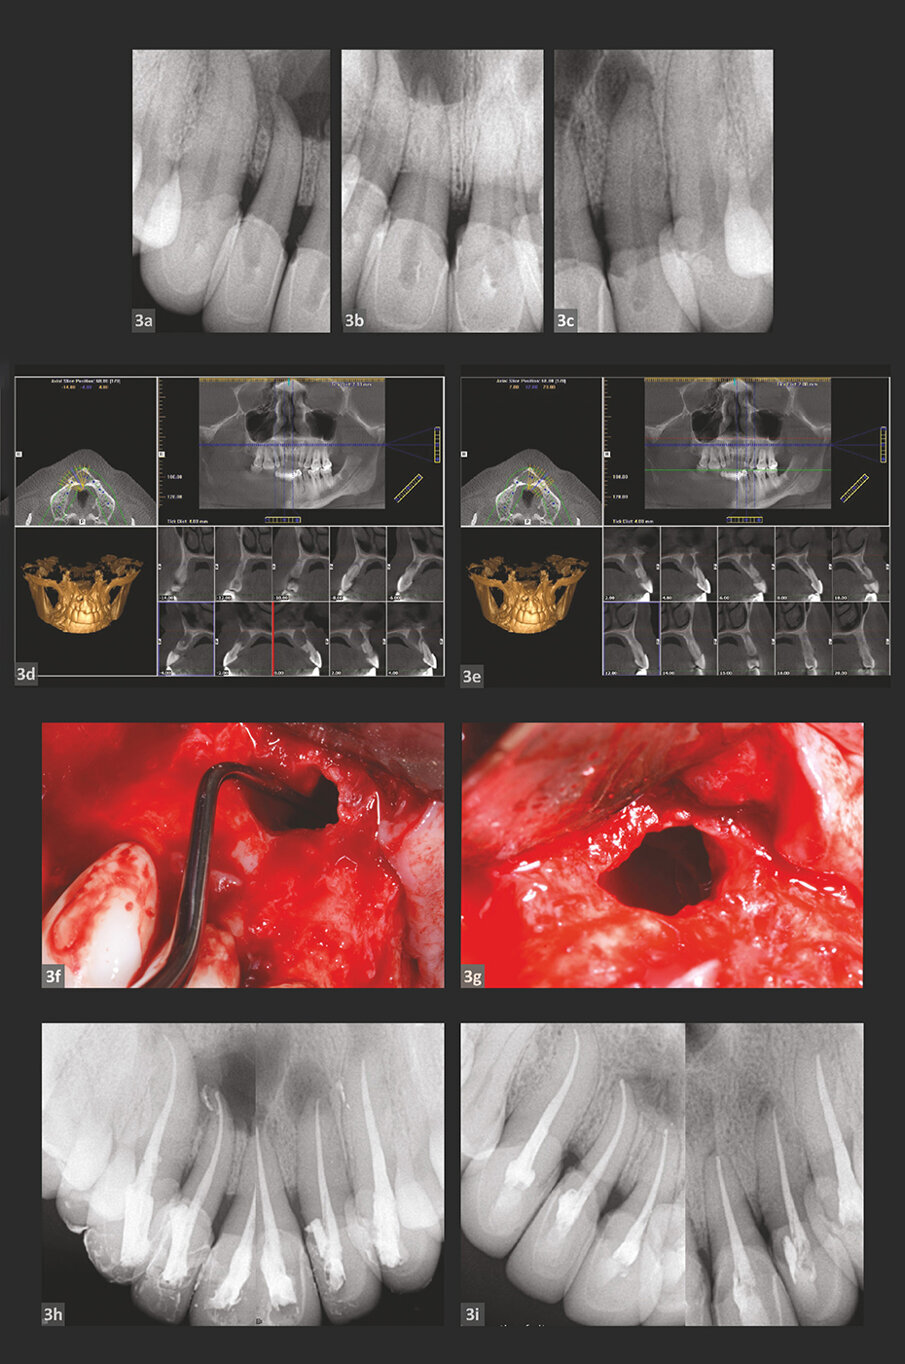

SLUČAJ 2

Slika 2a: Preoperativni periapikalni RTg snimak.

Slika 2b: CBCT podaci o pacijentu.

Slika 2c: Cistična reakcija u blizini mandibularnog kanala.

Slike 2d i 2e: Postoperativna radiografija neposredno nakon intervencije (d) u poređenju sa

preoperativna rendgenskom slikom (e).

Slika 2f: Jednogodišnje praćenje – Rtg snimak.

Slika 2g: Radiografija nakon dve godine praćenja.

Pacijent muškog pola upućen je na proveru mandibularnog molara. Za pacijenta je bilo bitno da spase njegov kutnjak svakako, iako mu je savetovano da ga izvadi i zameni implantatom.

Preoperativna radiografija (slika 2a) pokazuje značajnu periapikalnu leziju i prethodni stomatolog je stavio pastu kalcijum hidroksida u kanale.

Pored toga, pacijent se žalio na trnjenje u donjoj usni. i-CAT skeniranje (slika 2b) pokazalo je da cistična reakcija ide duboko unutra i skoro dostiže do mandibularnog kanala.

Izvršen je isti pristup, kao što je prethodno opisano, u pokušaju lečenja i spasavanja molara. Kada je režanj podignut, videlo se da je cista bila i ispod periosta iznad kortikalne kosti, a tu je bila još jedna cista pronađena intraoperativno blizu mandibularnog nerva (slika 2c), koji bi mogao biti odgovoran za osećaj trnjenja donje usne koji je pacijent prijavio.

Neposredni postoperativni rendgenski snimci (slike 2d i e) uzeti su po završetku hirurške intervencije i konvencionalne terapije kanala korena, a potpuno zarastanje je primećeno na kontrolnim rendgenskim snimcima nakon 1 i 2 godine (slike 2f i g) sa punom rekonstrukcijom kosti. Štaviše, u okviru prve 3 nedelje nakon tretmana peckanje donje usne je netsalo, kao i drugi klinički simptomi.